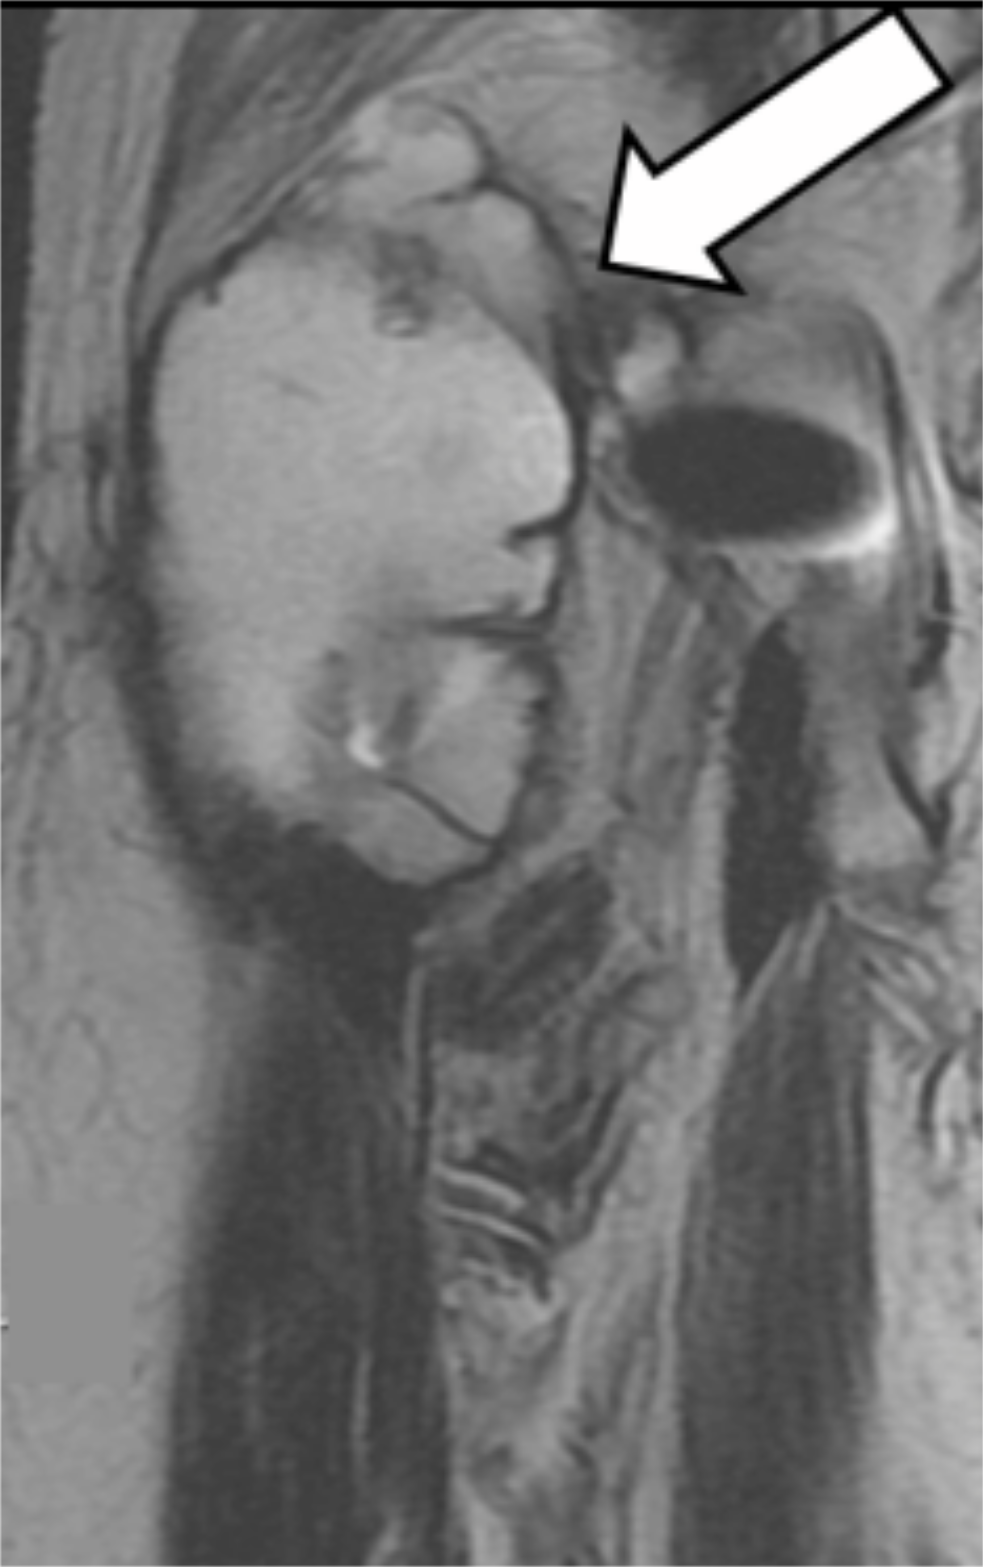

Magnetic resonance imaging (MRI) (Signa HDxt 1.5T Optima Edition GE Healthcare, Tokyo, Japan) demonstrated a large pseudotumor around the anterior hip joint (Figure 3).

Figure 3: T2-weighted coronal MR image in Case 1 (Arrow: pseudotumor).

Two months after surgery, she felt discomfort around the right hip joint, but no pain. Although she had a normal range of hip motion, she felt difficulty when she lifted her right leg, and needed a cane to walk. The symptoms continued up to revision surgery. Inflammatory serology was normal. Plain radiographs did not show any impending implant failure, but calcar osteolysis was visible 3 years after implantation (Figure 6). An ultrasound scan showed fluid collection around the hip joint. MRI demonstrated a large pseudotumor around the hip joint (Figure 7). Diagnosed as ARMD, revision surgery was performed.

Figure 8: T2-weighted coronal MR image in Case 2 shows a pseudo tumor (arrow).